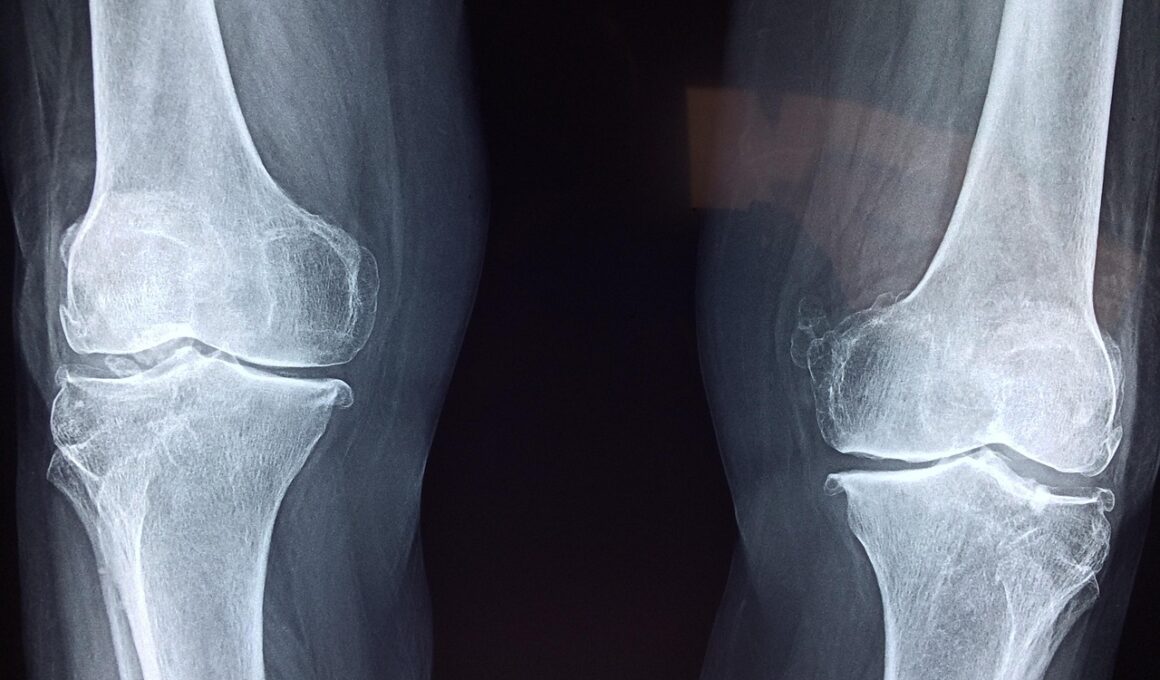

Another significant advantage of strength training for individuals with chronic conditions is its positive impact on joint health. Many patients suffer from joint pain and inflammation, hampering their ability to engage in physical activity. By strengthening the muscles surrounding the joints, resistance training provides more support, thereby reducing strain and discomfort. This effect is particularly beneficial for those with osteoarthritis, rheumatoid arthritis, and other inflammatory diseases. In addition to reinforcing muscle strength, strength training enhances joint stability and flexibility, leading to a greater range of motion. Patients often report decreased pain levels and increased mobility after a consistent strength training regimen. Furthermore, it fosters confidence in movement, encouraging individuals to participate in physical activities they might have previously avoided. Along with structured strength training programs, incorporating flexibility exercises, such as yoga or stretching, can further enhance mobility and relieve tension in affected joints. Ultimately, the complementary relationship between strength training and joint health highlights the multifaceted benefits that exercise can offer to individuals dealing with chronic illnesses.